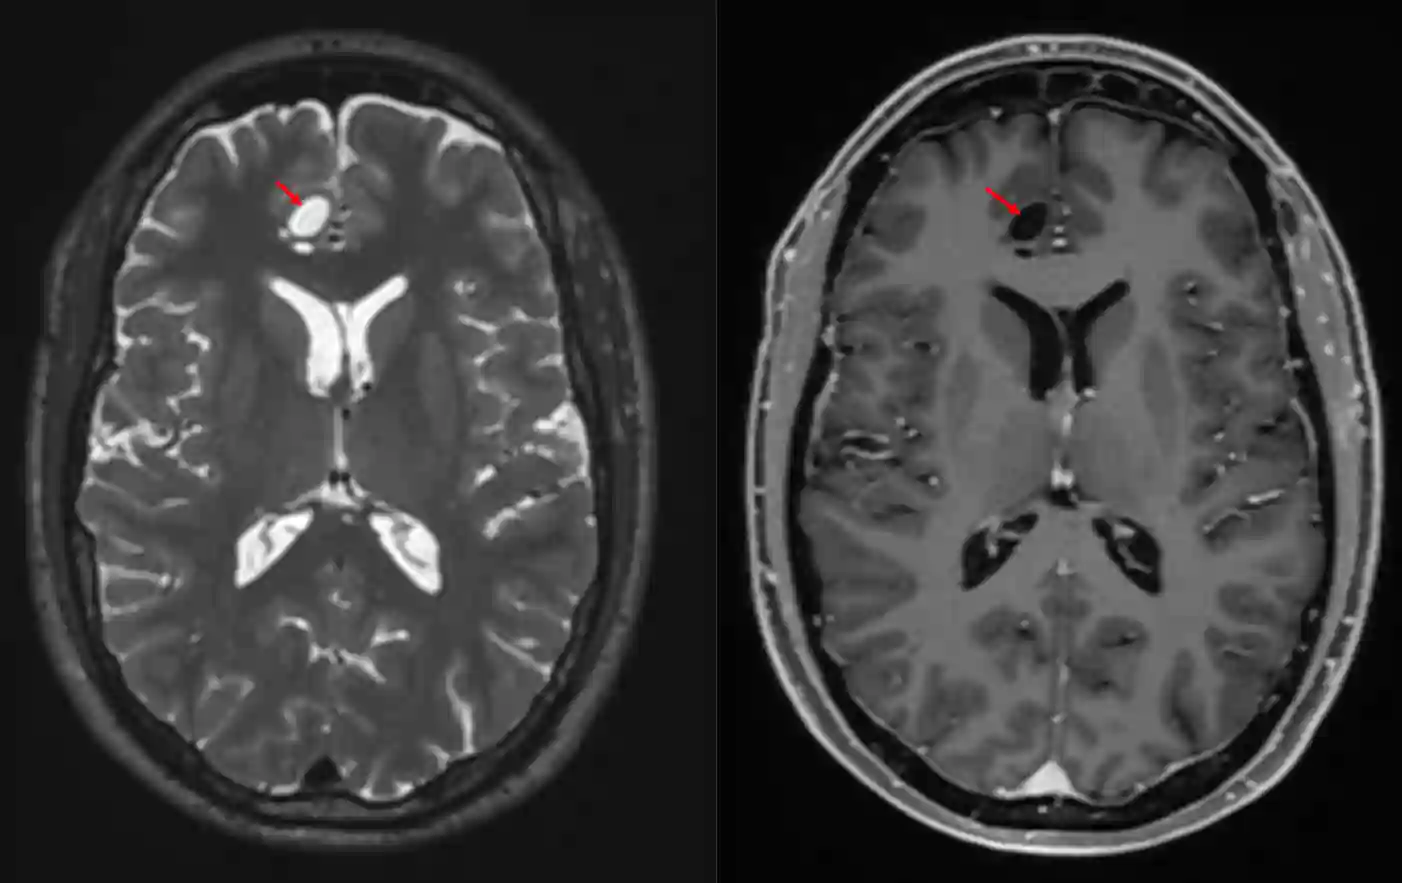

Im MRT zeigt sich bei einem MVNT Cluster von multiplen rund oder ovalen, intra-axialen Noduli, welche in der T2 und FLAIR Sequenz ein hyperintenses Signal haben5. MVNT sind meist als juxtakortikale Cluster zu finden und haben keinen Masseneffekt und keine Kontrastmittelaufnahme6.

Patient mit einem multinodular and vacuolating neuronal tumor of the cerebrum (MVNT) rechts frontal in einem axialen MRI Bild.